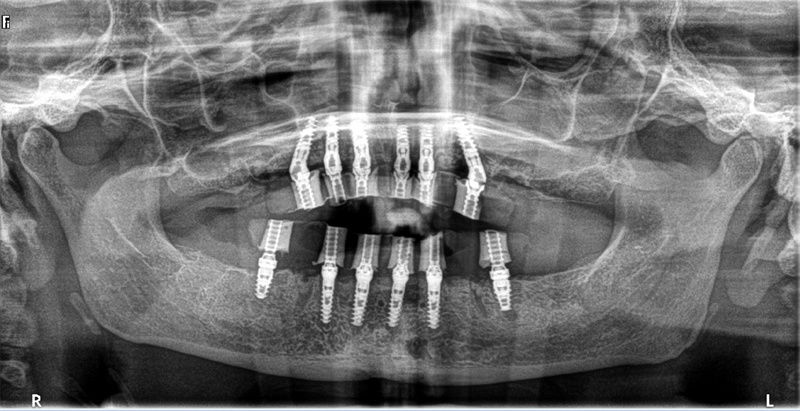

完成植入后全景照片